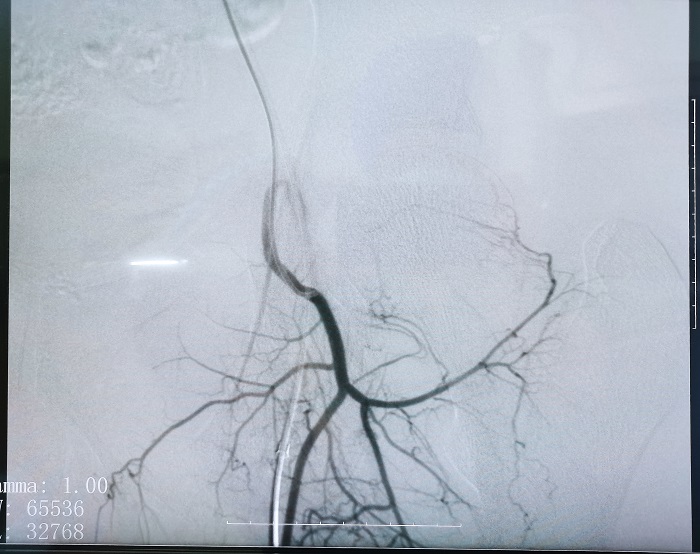

普爱平板介入中C在FTE手术过程中拍摄的造影图像

若根据HSG的诊断,患者存在输卵管积水,则可行输卵管栓塞术(Fallopian tube embolization, FTE),通过介入手段,注入栓塞剂或使用弹簧圈等器材进行栓塞,可以有效地阻断输卵管内的血流和组织,从而治疗输卵管积水。这个过程通常是在X线或超声引导下进行的,可以清楚地看到输卵管的情况。

输卵管栓塞的介入治疗作为输卵管积水的预处理是一项创新性的方法,也是行之有效的方法,所有操作都可在医学影像设备下进行,定位准确、操作简便。同时因为基本是微创手术,所以对卵巢功能无影响,可以有效改善输卵管积水引起的症状,如腹痛、腹胀等,并提高患者的生育能力,对体外受精-胚胎移植(IVF-ET)的发展有新的突破,妊娠率有显著性增加。